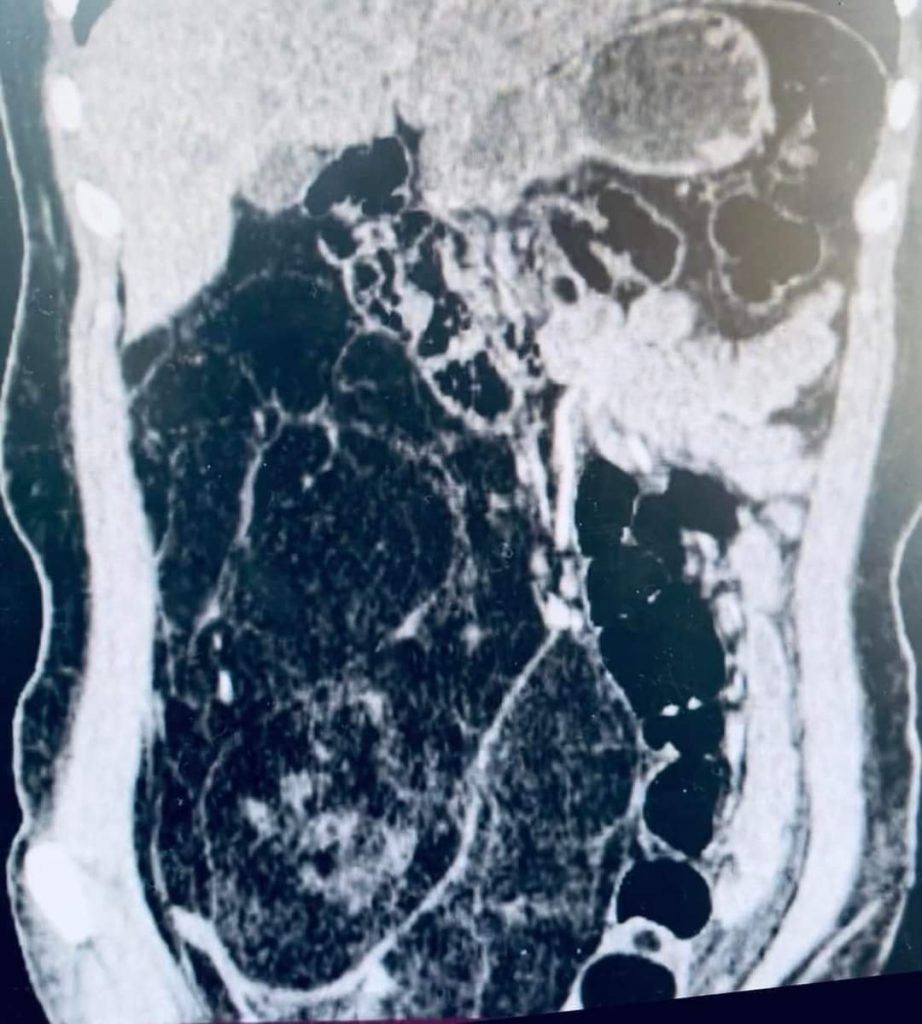

Хөвсгөл аймгийн нэгдсэн эмнэлгийн мэс засал, гэмтлийн тасгийн эмч нарын хамтарсан баг өвчтөний хэвлийн хөндийгөөс 3,2 кг хавдрыг мэс заслын аргаар авсан байна.

Тус мэс заслыг аймагтаа анх удаа 8 эмч, ажилтаны оролцоотойгоор амжилттай хийсэн нь олны талархлыг хүлээсэн төдийгүй орон нутгийн эмч нарын мэргэжлийн ур чадварыг харуулсан үйл явдал боллоо.

Дашрамд дурьдахад дөрөвдүгээр сард "Бриллиант" нэгдсэн эмнэлгийн ерөнхий мэс заслын тасагт 7,9 кг хэмжээтэй хавдрыг мөн хэвлийн хөндийгээс мэс заслын аргаар авсан тохиолдол гарсан.